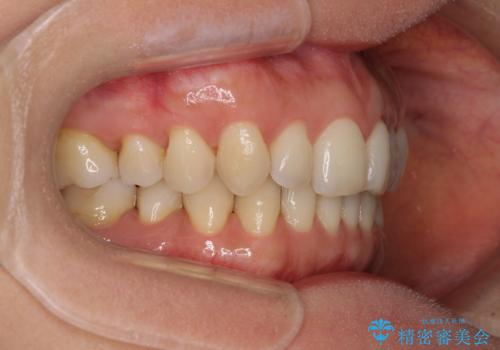

矯正治療の後戻り インビザライン・ライトによる矯正治療

- 患者様

- 40代女性

- 矯正装置

- インビザライン・ライト

- 治療期間

- 11ヶ月

- 矯正治療の後戻りを気にして来院された患者様です。

後戻りは軽微であったので、インビザライン・ライトにより矯正治療を行うこととしました。